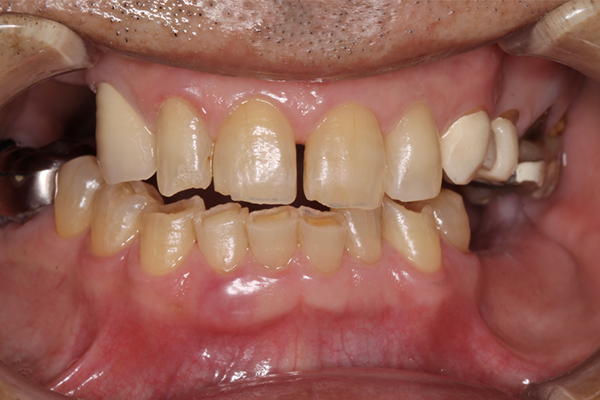

| 主訴 | 全体的にきれいにしたい |

|---|---|

| 治療内容 | 午前中に上下顎共に重度の歯周病、虫歯のため全ての歯を抜歯させていただき下顎はインプラントの土台を3本埋入し歯型を取り午後に上部構造(下顎全ての歯)を装着、上顎は一度総入れ歯を装着させていただきました。 治療が1日で完了しその日のうちに噛めるようになります。 |

| 治療期間 | 2回(1回目に資料取りをさせていただき2回目に下記の全ての治療をさせていただきました。) |

| 治療費 | 250万円 |

| 治療 リスク | 抜歯した部位などに関しては当日痛みが出ますので痛み止めなどを処方させていただきます |